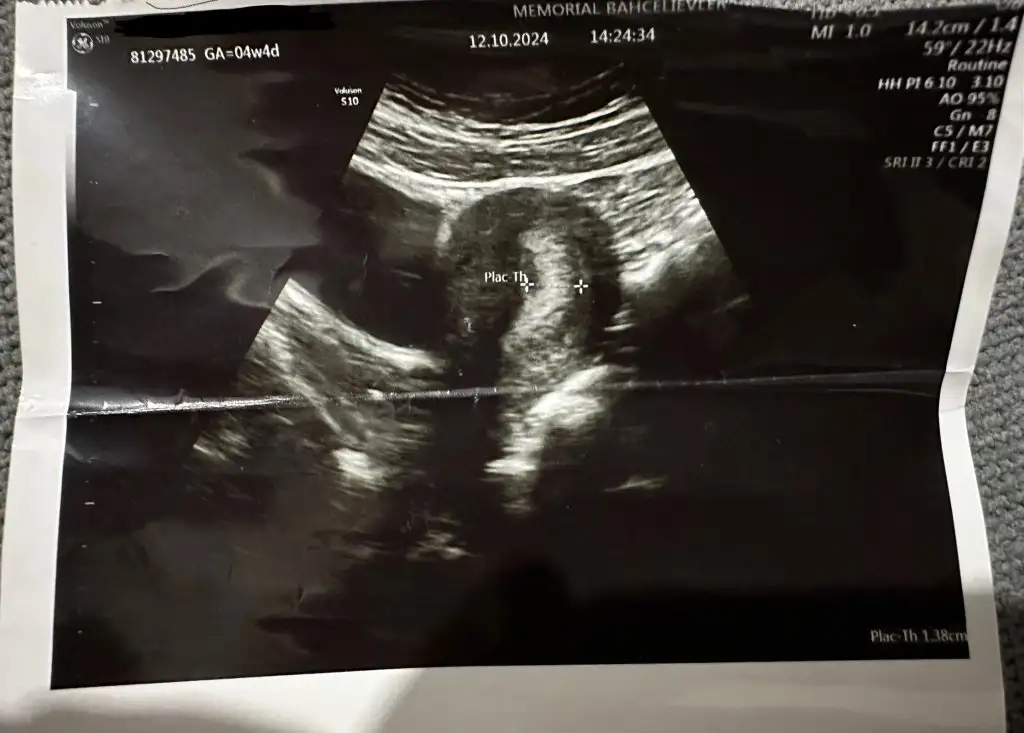

Normalde içiyormuydun ?Hiyy Hiyy yuhum gelir tam o noktadayım bi de masa başı oturmaktan belim ağrıdı ya odaya koltuk isticem yüzsüzlük olcak diye isteyemiyorum tek istediğim uzanayım uyuyayım sigara da Allaha büyük konuşmayım ama içmicem organları sımdı den olusuyomuş korktum![]()